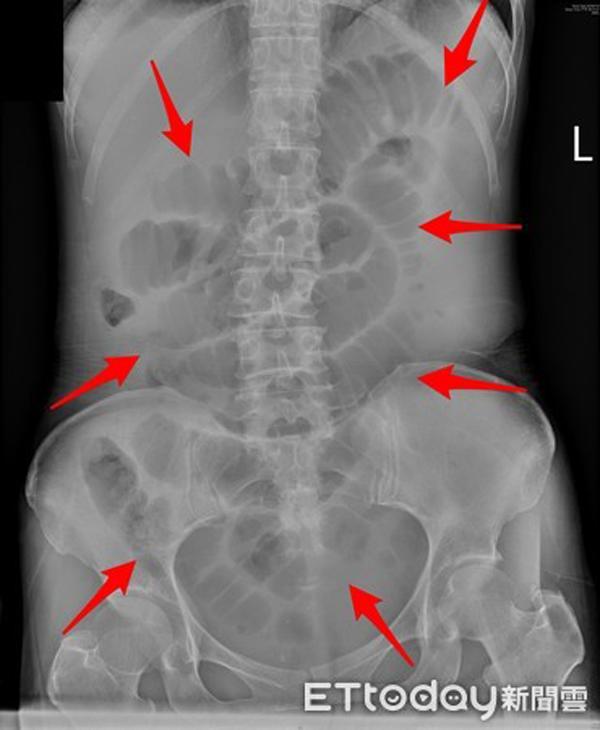

Một người phụ nữ 51 tuổi đã phải tới bệnh viện vì táo bón nhiều ngày, bà thậm chí còn không thể “xì hơi”. Sau khi kiểm tra, bác sĩ nhận thấy trong ruột của bệnh nhân chứa đầy chất thải, chiếm gần như toàn bộ khoang bụng khiến cho ruột bị sưng to.

Ruột người phụ nữ bị phình to do tắc chất thải.